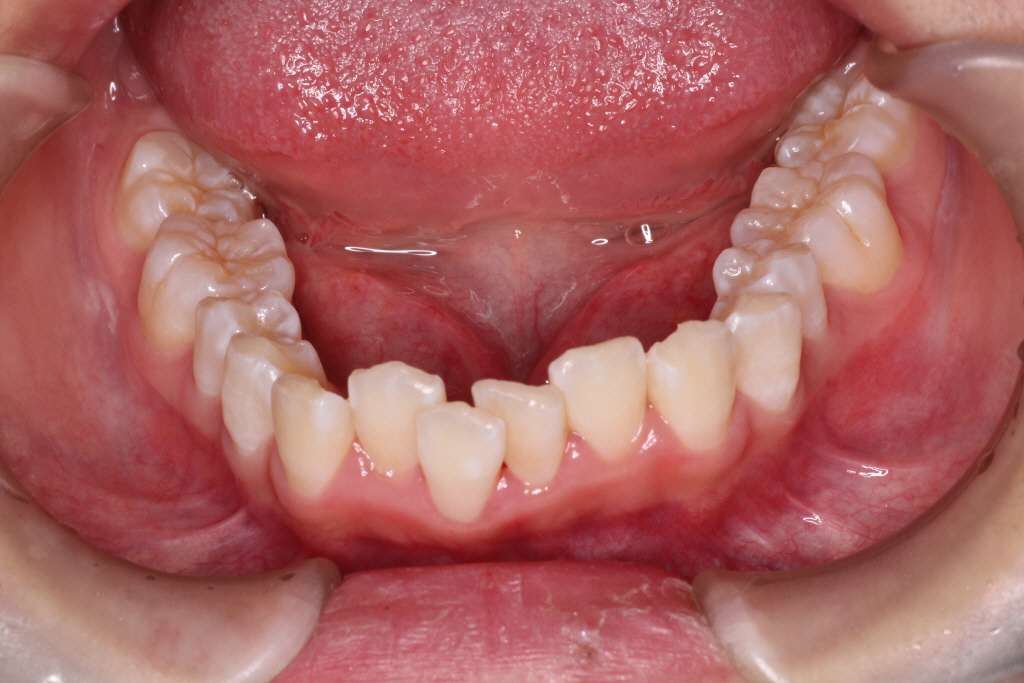

カリエールモーションが終わった時の口腔内写真です。

上の奥歯が後ろに下がったおかげで前歯には隙間ができています。

左の噛み合わせを見ると下の歯と歯の間に上の歯が入り込んでいることがわかります。

1歯対2歯の関係です。

右の噛み合わせを見ると左の噛み合わせより少し多めに奥歯を後ろに下げていることがわかります。

オーバーコレクションといって少し戻ることを想定して多めに動かしておくことを言います。